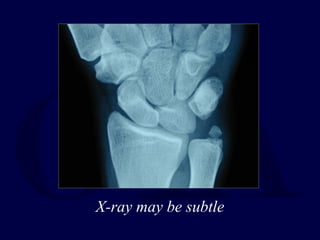

X-ray usually

Obvious

X-ray may be subtle